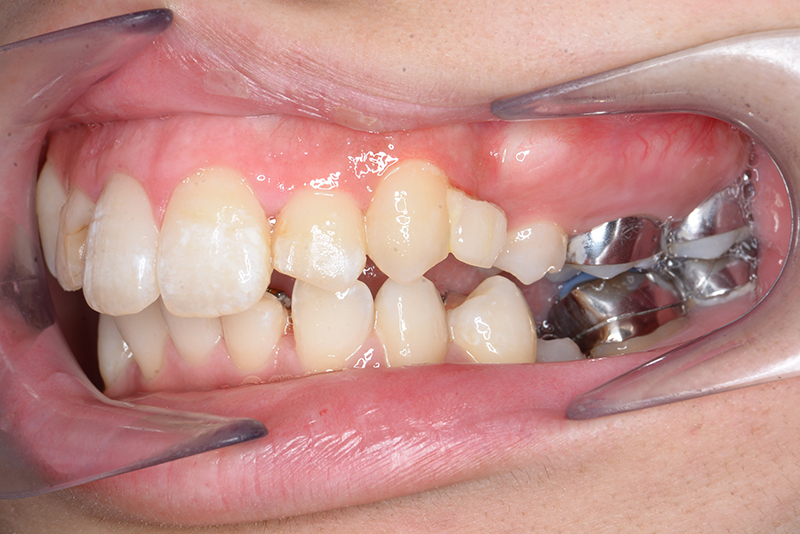

動的治療中のIOP(治療開始後6ヶ月)

動的治療中のIOP

(治療開始後6ヶ月)